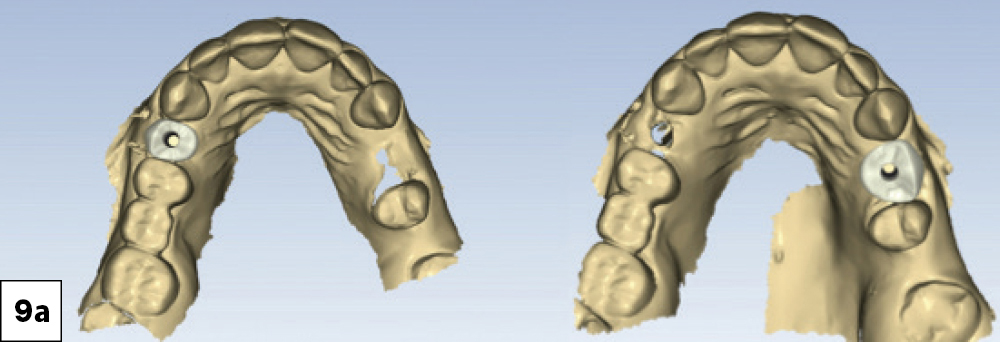

Two screwretained crowns were designed with precise occlusal morphology and customized emergence profiles to support the peri-implant soft tissue-a

Two screwretained crowns were designed with precise occlusal morphology and customized emergence profiles to support the peri-implant soft tissue-b

Figures 9a, 9b: Using the AI-assisted design tools in the fastdesign.io software, which allow for automatic alignment of scan body scans, the design process can be completed in about 10 minutes. Two screw-retained crowns were designed with precise occlusal morphology and customized emergence profiles to support the peri-implant soft tissue. The integrated Ti-base geometry within the block ensured that the digital design translated seamlessly into the physical restoration, maintaining the precision of the connection and allowing the restorations to be delivered immediately after milling, without the need for sintering, bonding, or additional post processing.